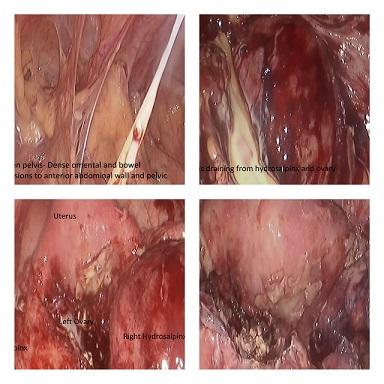

MINIMAL ACCESS SURGERY IN A FROZEN PELVIS. 28 yea...